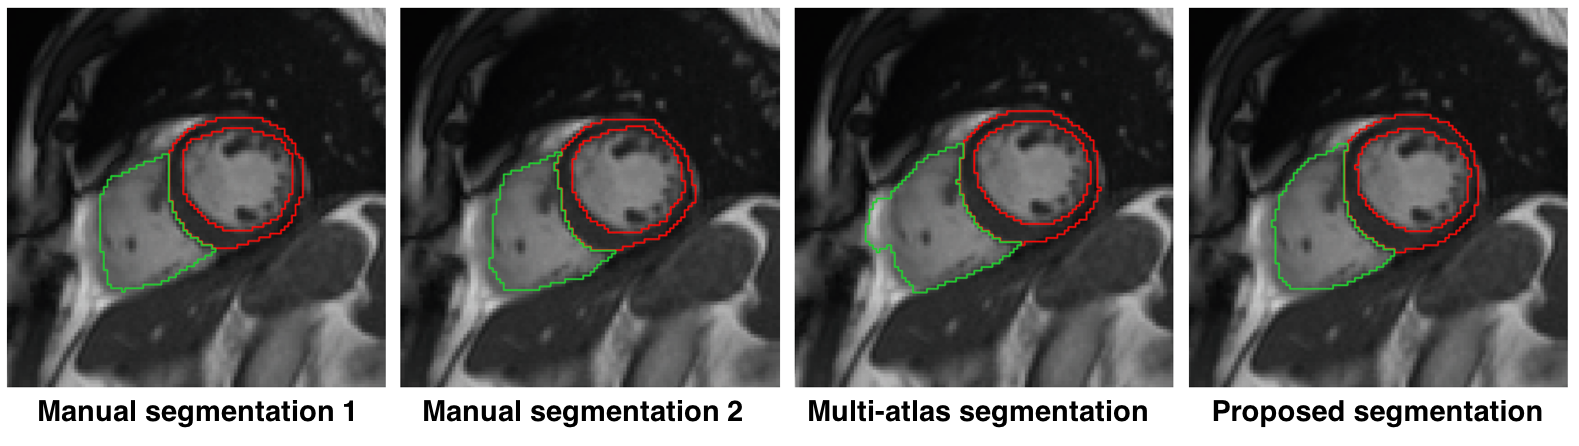

4) a semi-supervised learning approach for network-based segmentation of CMR image stacks. This technique achieves cardiac segmentation with an accuracy comparable to that of human interpreters (see Fig.3). Scientific dissemination was performed with a presentation at an international conference (MICCAI 2017) with an accompanying short paper and with the submission of a journal paper (now undergoing revision);